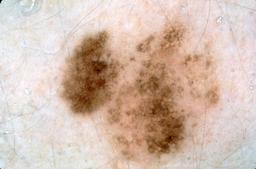

{

"age_approx": 70,

"anatom_site_general": "lower extremity",

"concomitant_biopsy": true,

"dermoscopic_type": "contact non-polarized",

"diagnosis_1": "Benign",

"diagnosis_2": "Benign epidermal proliferations",

"diagnosis_3": "Solar lentigo",

"diagnosis_confirm_type": "histopathology",

"image_type": "dermoscopic",

"lesion_id": "IL_9273672",

"melanocytic": false,

"patient_id": "IP_4306446",

"sex": "female"

}